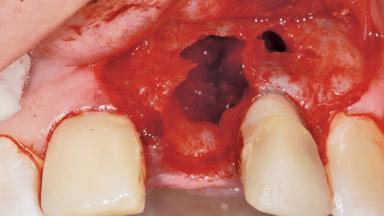

Late Placement of an Implant in a Maxillary Left Central Incisor Site

A 36-year-old female patient was referred for the replacement of the upper left central incisor (tooth 21), which had fractured. Although the tooth had been asymptomatic for many years, the crown began to loosen, at which time she presented to her dentist for an assessment. Teeth 21 and 22 had both been endodontically treated many years previously. She was a healthy individual and a non-smoker.

The crown of tooth 21 was splinted to the adjacent teeth with composite resin, and the gingiva was inflamed.

Bone Augmentation Horizontal|Staged

Augmentation Materials Xenogenous|Membrane

Soft Tissue Anatomy Intact Defective

Bone Volume Horizontally and vertically sufficient Horizontally deficient Deficient vertically or deficient vertically AND horizontally

Bone Volume Deficient horizontally, requiring prior grafting